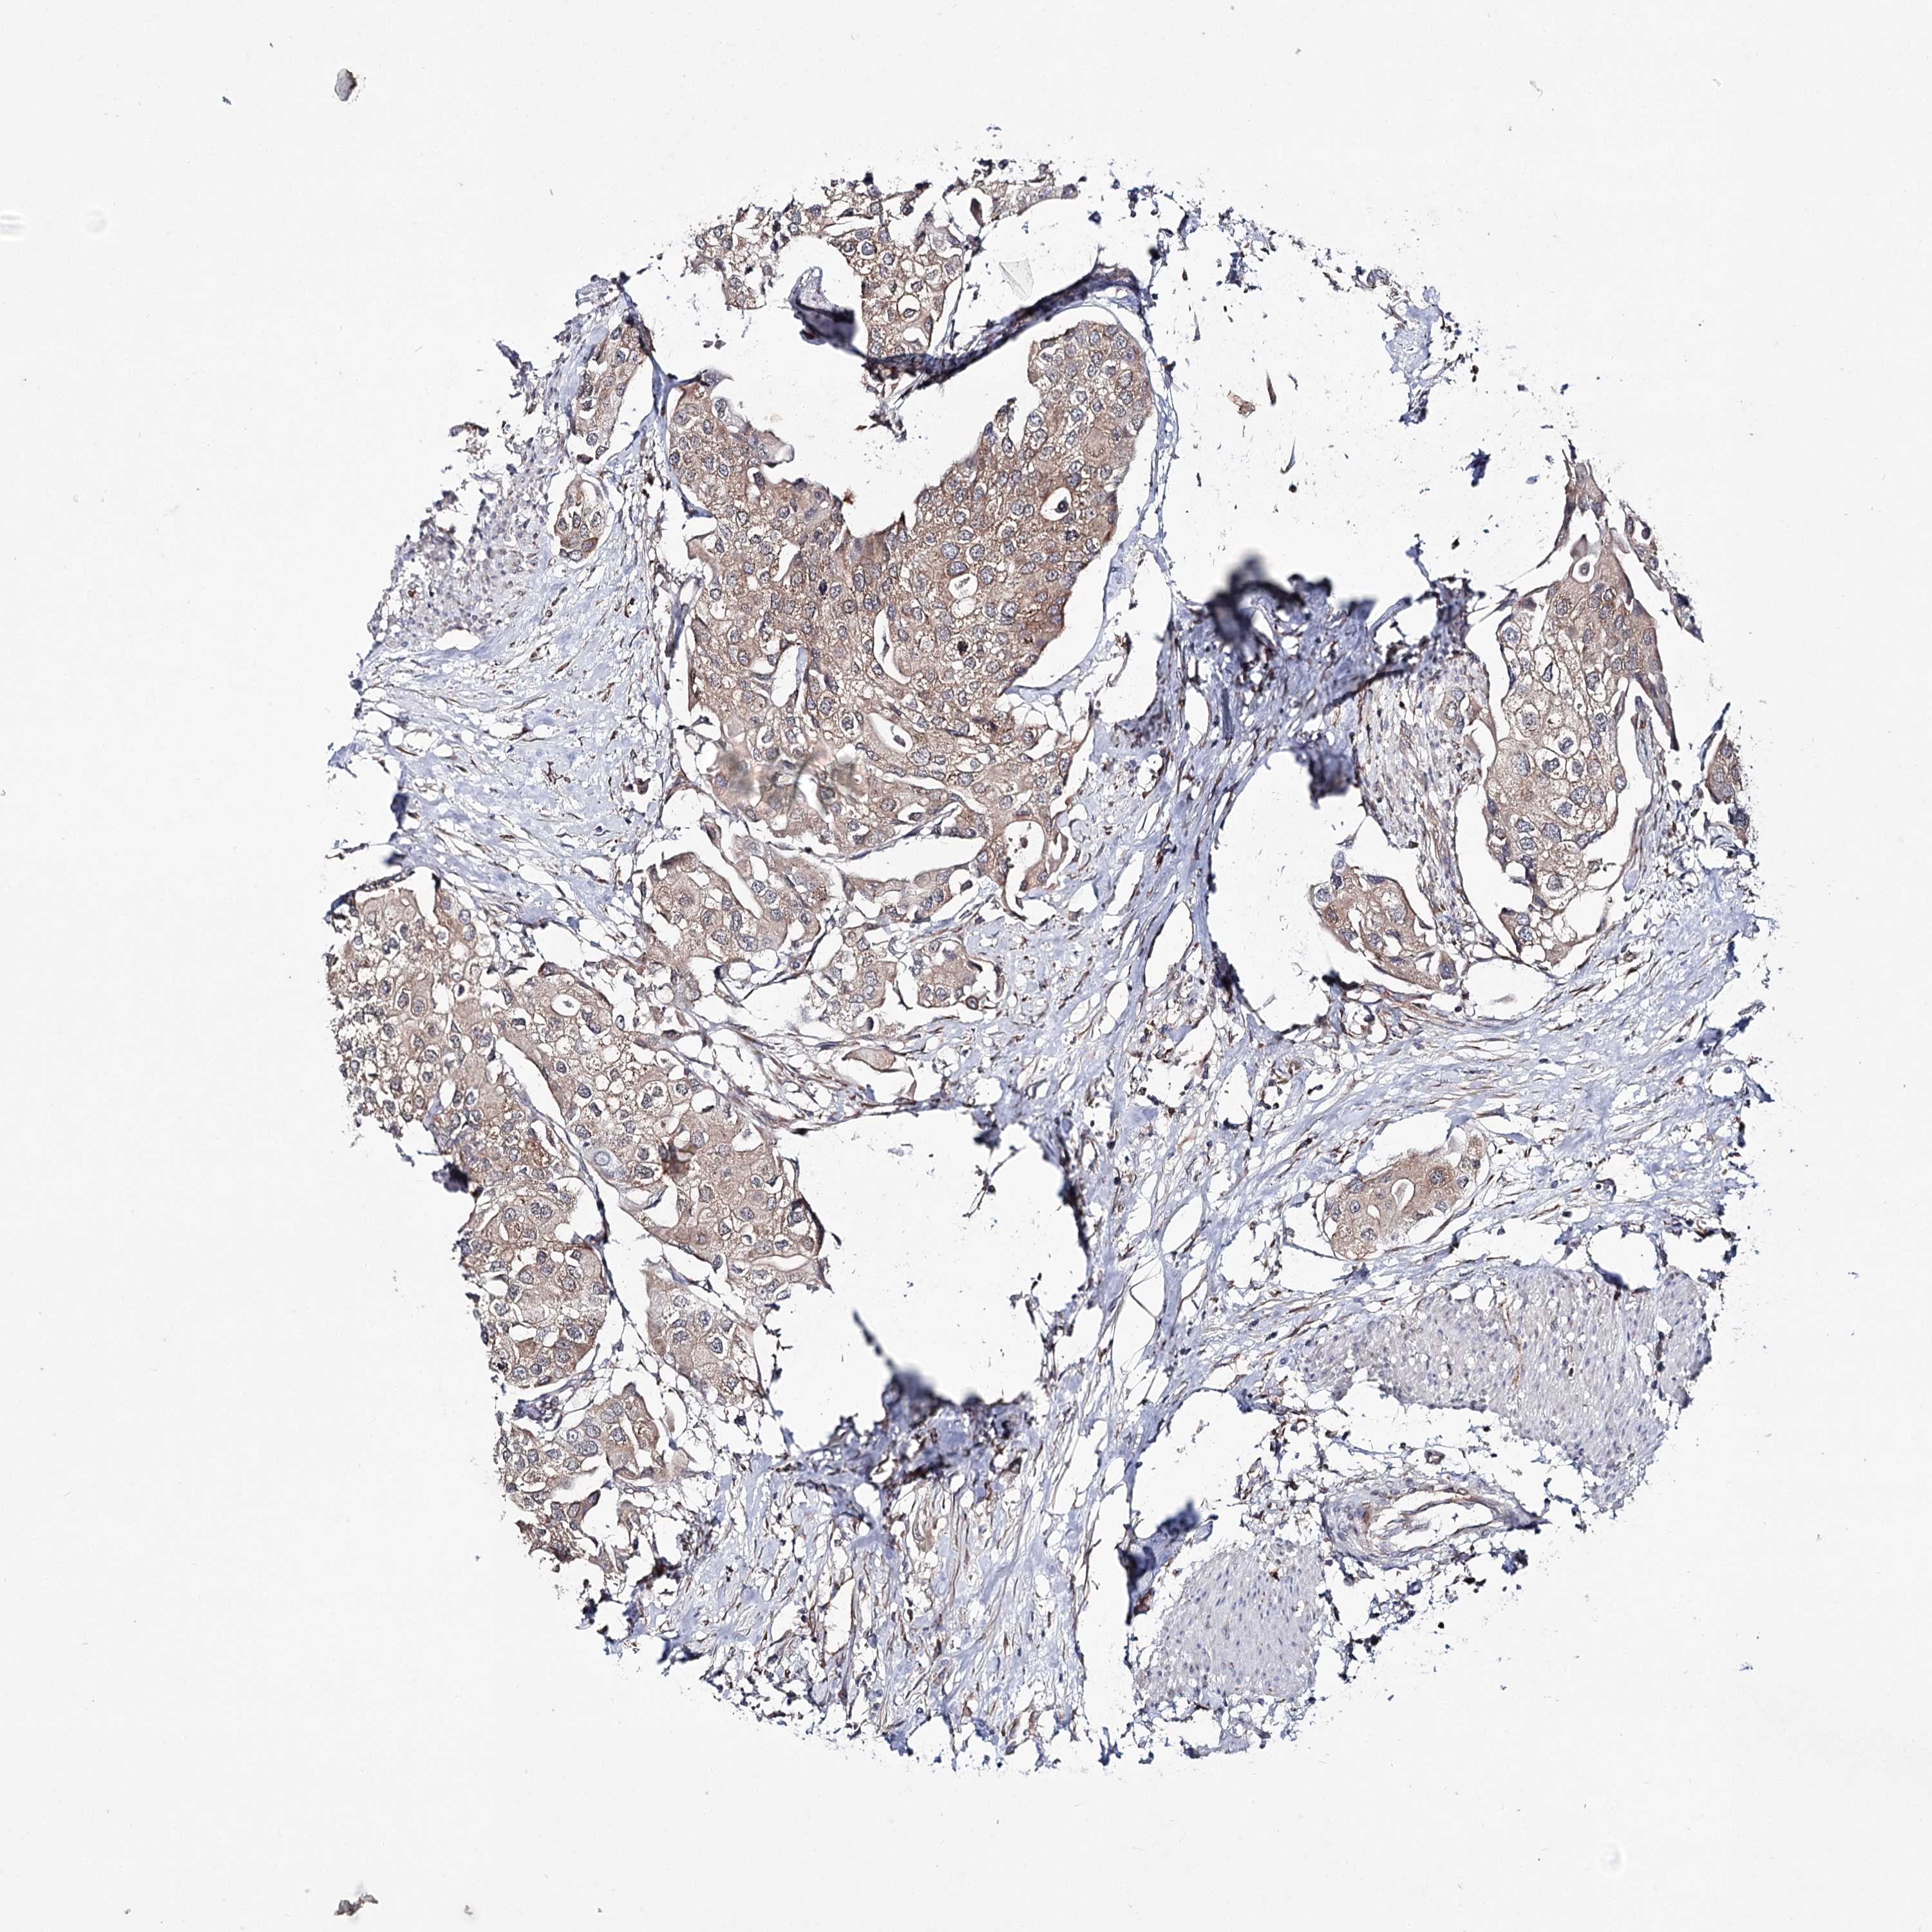

UROTHELIAL CANCER - Protein expressioni

A mouse-over function shows sample information and annotation data. Click on an image to view it in a full screen mode. Samples can be filtered based on level of antibody staining by selecting one or several of the following categories: high, medium, low and not detected. The assay and annotation is described here.

Note that samples used for immunohistochemistry by the Human Protein Atlas do not correspond to samples in the TCGA dataset.

Antibody stainingi

Antibody staining in the annotated cell types in the current human tissue is reported as not detected, low, medium, or high, based on conventional immunohistochemistry profiling in selected tissues. This score is based on the combination of the staining intensity and fraction of stained cells.

Each image is clickable and will lead to virtual microscopy that enables deeper exploration of all samples and also displays staining intensity scores, fraction scores and subcellular localization as well as patient and tissue information for each sample.

Antibody HPA037847

Staining

High

Medium

Low

Not detected

Intensity

Strong

Moderate

Weak

Negative

Quantity

>75%

75%-25%

<25%

None

Location

Nuclear

Cytoplasmic/membranous

Cytoplasmic/membranous,nuclear

Urothelial carcinoma, High grade

Urothelial carcinoma, Low grade

Urothelial carcinoma, NOS